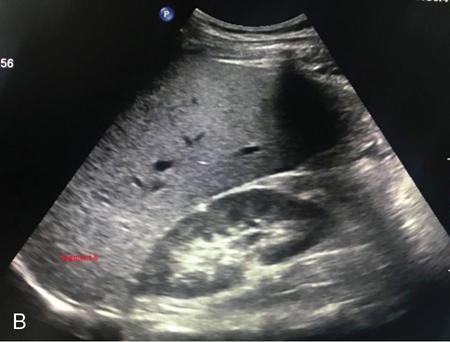

Samarjit Ghuman, Seema Sud, Deeksha Rastogi, Swapnil Sheth, T.B.S. Buxi PLAIN RADIOGRAPHY FOR HEPATOBILIARY IMAGING The diagnostic imaging techniques for hepatobiliary imaging can be intimidating with many techniques/modalities providing the information desired. The job of the diagnostic radiologist includes being familiar with the available choices and pick the ‘best fit’ keeping in mind the pros and cons of each modality, which includes plain X rays, Contrast studies using plain X rays and fluoroscopy, Ultrasound includiojng Doppler and Ultrasound elsastography, CT including multiphase CT and MRI and MRI elastography. Understanding the strengths and weaknesses of every modality as well as the ability to tailor each study individually will help to optimise patient cares. The abdominal radiograph is performed almost exclusively in the supine position and in the AP (anteroposterior) projection. In case of acute abdomen, an erect chest radiograph should also be performed to look for free air under the diaphragm. The standard abdominal radiograph should extend from the diaphragm to the inferior pubic rami, and includes the lateral abdominal wall musculature. Routinely no preparation is required for abdomen radiograph done for hepatobiliary imaging. The radiograph has limited soft-tissue contrast, however, the liver being the largest intra-abdominal organ, casts a perceptible shadow. The margins of the liver can indirectly be seen by outline of adjacent organs like lung, hemidiaphragm, pro-peritoneal fat line, kidney and gas shadows of stomach/colon. The right lobe is seen better than the left lobe of liver. The following pathologies may be visualized on the plain radiograph of the liver. Liver enlargement Liver mass Calcification Increased radiodensity of the liver Decreased radiodensity of the liver An ultrasound is the first line investigation; however, a radiograph may be done for routine evaluation of abdominal pain. The following pathologies may be seen on plain radiograph of the biliary tree. Calculi and Calcifications Gas ULTRASOUND OF HEPATOBILIARY SYSTEM Ultrasonography (USG) is the initial imaging modality of choice for scanning hepatobiliary system. USG is accurate and has high sensitivity and specificity in diagnosing biliary pathologies. Table 9.1.1 shows indications of ultrasound in hepatobiliary system. The real-time nature of ultrasound lends itself to demonstrate mobility of calculi and sludge and the sonographic Murphy sign can easily be elicited during scanning. The main disadvantage is operator dependence, patient’s body habitus, presence of gas which can obscure the visualization of organs, overlying bandages in a postoperative patient and incomplete evaluation in a nonfasting state. USG of upper abdomen should be done after 6–8 hours of overnight fasting. Milk and fatty food should be avoided as they cause contraction of the GB and may cause the GB walls to appear thickened. History of previous surgery, especially cholecystectomy should be elicited. The patient may be positioned in supine or left lateral decubitus position. The GB can be scanned from a high/lateral view, looking through the ribs in supine position or through a sub-costal view in left lateral decubitus position. Position of patient may be changed to demonstrate mobility of structures. The GB is an anechoic structure which is located in the GB fossa along the posterior and inferior aspect of the liver. It has a fundus, body and a neck. It should always be examined in at least two planes (Fig. 9.1.6A and B). The wall of the normal GB should measure 3 mm or less and pathological GB wall thickening can be due to cholecystitis or a neoplastic aetiology. Calculi appear as mobile hyperechoic foci, with distal acoustic shadowing. Other pathologies include polyps and sludge which can be differentiated on the basis of their mobility. The CBD measures less than 6 mm in diameter with increase in the diameter with patient’s age and after cholecystectomy. The CBD is usually scanned in an oblique subcostal plane with the patient in the left decubitus position (Fig. 9.1.7). Dilatation of the intrahepatic biliary radicles is readily assessed with USG and normal intrahepatic biliary radicles are usually not appreciated on USG. Ultrasound of the liver, broadly, is done to assess the size, surface (smooth, coarse or lobulated) parenchymal echogenicity (increased or decreased) vascularity and for presence and evaluation of intrahepatic masses or fluid collections. The liver is divided into right and left lobes by plane of middle hepatic vein which passes through GB fossa and notch of IVC (Cantlie Line). Couinauds classification is the most commonly used system for liver segmental anatomy and described liver into eight functional segments. It is based on distribution of portal and hepatic veins. Every segment has its branch from portal vein, hepatic artery and bile duct (Fig. 9.1.8). Curvilinear transducer (3–5 MHz) is used for routine examination of liver and GB (Fig. 9.1.9). A high-frequency linear transducer (9–11 MHz) (Fig. 9.1.10) can be used to look for subtle irregularity of the liver surface for early Cirrhosis and fine details of GB wall. The liver is scanned in deep inspiration, which causes inferior movement of liver, so that superior borders of the liver are well visualized. Supine position is used for the size of the liver. The measurement is made in sagittal mid clavicular position on right side, in craniocaudal dimension. It is taken from diaphragm to the lower end of the liver. It should be <16 cm and varies with age and sex. The liver is divided into four vertical sectors by three hepatic veins and plane of bifurcation of portal vein divides these 4 sectors in to 8 segments. The right hepatic vein creates vertical plane in the right lobe separating segments V and VIII (anterior) from VI and VII (posterior). The portal vein bifurcation creates a transverse plane and divides these segments into superior (VII, VIII) and inferior segments (V, VI). The left hepatic vein divides the left lobe into medial (IVa, IVb) and lateral sectors (II, III). The left portal vein divides left lobe into superior (Iva, II) and inferior segments (III, IVb). The middle hepatic vein separates medial segments of left lobe (IVa, IVb) from anterior segments of right lobe (V, VIII). Ligamentum teres separates segment III from IVb. Ligamentum venosum separates segment I from IV and II. Cystic duct is an anechoic tubular structure which connects neck of the GB to the extrahepatic biliary tree. In long axis view of GB, the neck of the GB is related to main lobar fissure which appears as a linear echogenic line which runs obliquely between neck of GB and right portal vein. In the right oblique sub coastal view CBD is seen anterior and parallel to portal vein. A series of standardized sections or views may be obtained for liver scanning. Transverse Subcostal View: In this view the probe is angled cephalic and placed transversely under the ribs on the right side and portions both lobes of the liver can be seen (Fig. 9.1.11). Mid Transverse View (Fig. 9.1.12) in this transducer is kept in transverse plane in the midline below the xiphisternum. It visualises the liver in an inferior to superior transverse oblique plane and portions of both lobes of liver can be seen along with right and left portal veins. This view is obtained by angling the transducer superiorly toward the hepatic venous confluence. In this view, we can see the three hepatic veins joining the IVC. Right Parasagittal View for Both Right Lobe and Kidney: This view allows assessment of inferior right lobe of liver. It also allows assessment of relative echogenicity of liver and renal cortex as both are seen together in the same image. Normal liver parenchymal echogenicity is greater than renal cortex and less that renal medulla (Fig. 9.1.14). Parasagittal Right MidClavicular View: In this transducer is kept in sagittal plane in right midclavicular line, and oriented supero-inferiorly. This is the standard view for assessing craniocaudal span of liver (Fig. 9.1.15). Parasagittal View for the Left Lobe: For evaluation of left lobe of liver and lateral segments (2 and 3) (Fig. 9.1.16). This view is obtained along the direction of the main portal vein. CEUS of the liver is done to evaluate Focal Liver Lesions and complements traditional B mode ultrasound and Doppler study. It is a simple, accurate and cost-effective tool complimenting indeterminate CT and MRI findings or for characterization of lesions in patients who cannot receive CT/MRI contrast and can be used in patients with compromised renal function, with minuscule risk of side effects. As CEUS is real-time, microvasculature can be studied along with tissue perfusion kinetics. Indications and uses of CEUS: Contrast agents and technique: Interpretation: Contrast-enhanced ultrasound of a hepatic hemangioma in different phases (Fig. 9.1.19). Limitations of CEUS: Liver elastography is a noninvasive method for diagnosing liver fibrosis. Liver fibrosis is induced by chronic liver disease leading to cirrhosis and liver cancer. Liver biopsy is the gold standard for diagnosing the degree of fibrosis and for staging but it is an invasive method. Elastography helps in analysing the elasticity or the stiffness of the tissue. A stiffer liver tissue indicates fibrosis or chronic liver disease. ARFI is based on the principle of measuring Shear wave velocity. Short duration acoustic pulses which are generated in the tissue and these give rise to shear waves which travel, perpendicular to the ultrasound beam. These shear waves cause tissue displacement followed by recovery. This displacement and recovery depend on tissue stiffness. To monitor these shear waves US beams of low intensity are emitted continuously parallel to the main beam along with the push pulses, and these beams can gather data regarding the tissue stiffness. The shear waves cause tissue displacement and this tissue then recovers from the impulse. From this data the degree of tissue stiffness can be obtained which is displayed either as a map or quantitatively where tissue elasticity is expressed as shear wave velocity measured in meters per second. F0, normal; F1, enlarged fibrotic portal tract; F2, periportal/initial porto-portal septa with intact architecture; F3, architectural distortion with no obvious cirrhosis; F4, cirrhosis. It is also known as Transient Elastography (TE) and works on the similar principle as ARFI, the difference being that B mode ultrasound image is not produced. DOPPLER OF PORTAL VEIN The portal vein divides at the portahepatis into right and left branches. The right portal vein divides into anterior and posterior branches, and the left portal vein divides into medial and lateral branches. Portal vein shows a continuous, forward low-velocity flow (15–28 cm/s) on colour Doppler scanning. The flow is hepatopetal, that is, towards liver and is red in colour as it is flowing towards the transducer. It has an undulating pattern and shows respiratory variation with increase flow in inspiration. It may reflect cardiac variation and shows postprandial increase calibre and flow in healthy individuals. Normal Doppler waveform of portal vein (Fig. 9.1.22). Portal hypertension can be defined as elevated pressure within the portal venous system resulting in impaired blood flow through the liver. INTRAOPERATIVE PANCREATIC AND HEPATIC ULTRASOUND Intraoperative ultrasonography of the pancreas was first described in 1980 by Lane and Glazer. It is an important technique for guidance of both open and laparoscopic surgical procedures of the pancreas. As the transducer is in direct contact with the organ of interest, with no interference with air of adjacent soft tissue, it provides good resolution. It is considered superior to CT and MRI in assessing the intraoperative tumour resectability and vascular invasion and guiding resection. Indications and uses For intraoperative US during open surgical procedures, a high-frequency linear-array transducer or the hockey stick transducer (Fig. 9.1.23) are used which create high-resolution detail of the exposed pancreas. The side-fire curved linear-array transducer is effective for obtaining a wider view of the pancreas and its surrounding structures and for scanning the liver. Intraoperative hepatic ultrasound gives the real-time visualization of the hepatic anatomy and aid for surgical planning and making decision during surgery. Indications and uses Transducer and technique Limitations MULTIDETECTOR CT OF THE HEPATOBILIARY SYSTEM AND CHOLANGIOGRAPHY The cross-sectional plane of the patient is denoted as the x/y plane. The plane along which the table moves is the ‘z’ plane. Multidetector CT denotes more than one detector along the Z-axis, with the latest machines having up to 320 and now even 640 rows of detectors. This provides CT with very fast, high resolution, isotropic images which can be reconstructed in any plane or even curved planes. MDCT scanners can comfortably scan the entire abdomen in 10 seconds or less, thereby allowing visualization of different phases of contrast enhancement. Contrast Media (CM) after administration gets distributed from the intravascular compartment into the interstitial spaces. Intravascular arterial enhancement (for angiography) and parenchymal enhancement have different kinetics. Parenchymal enhancement is directly proportional to total iodine dose being administered and inversely proportional to weight, which is a marker of extracellular volume into which contrast redistributes. Rate of iodine administration has no effect on degree of parenchymal enhancement. As a general rule approx. 500–600 mg of iodine/kg body weight achieves adequate hepatic parenchymal enhancement. For a 60 kg adult, this translates into approx. 100–120 mL of contrast containing 300 mg of iodine per mL. Intravascular or arterial enhancement is controlled by rate at which iodine is administered (flow rate and iodine concentration of CM) iodine flux and duration for which contrast is administered longer injection also leads to better overall arterial opacification due to recirculation effects. This principle is made use of while performing abdominal CT Angiography. Higher iodine delivery rate per unit time using a higher iodine concentration contrast medium also improves conspicuity of vessels and hypervascular lesions such as HCC. For identical parameters, difference in arterial enhancement between patients is dependent on cardiac output with enhancement being inversely proportional to cardiac output. For optimal imaging and enhancement, in multiphase imaging and angiographic studies, contrast material administration and parenchymal or vascular enhancement must be synchronized with CT data acquisition. The two main methods are: Test bolus technique: A test dose of contrast is given and the time to peak enhancement is measured in a ROI placed in a target vessel this information can be used to tailor CT acquisition. Automated bolus Triggering: ROI is placed in target vessel (usually aorta at level of diaphragm) on a plain image. While CM is injected, a series of low dose scans is obtained through the ROI. When the density of contrast reaches a predefined threshold (e.g. 150 HU), at time ‘t’ the scan is automatically triggered. The trigger delay after time ‘t’ is a minimum of 2 sec, and can be programmed to any value. Bolus tracking is nowadays the method of choice for planning contrast medium administration and this technique provides more homogenous opacification. Saline chase is recommended in all multiphase protocols. Significant amount of contrast may be present in the peripheral veins after injection of IV contrast and use of saline chaser leads to better vascular enhancement and lower overall contrast dose (Fig. 9.1.24). Using the above, a standard sequence of acquisitions and contrast enhancement techniques can be tailored to the pathology and organ of interest and pre-programmed into the scanner menu, which includes kVp, mAs, pitch, rotation time, slice thickness etc. This is known as a scan protocol. However, these can be modified as necessary. For example, rotation time can be shortened and pitch can be increased for breathless patients to reduce scan times (Table 9.1.4). Multidetector CT is the workhorse of hepatobiliary imaging. It plays a major role in imaging congenital, traumatic, infective, neoplastic and vascular pathologies of the hepatobiliary system. Scans can be obtained with or without intravenous (IV) iodinated contrast material administration. Multidetector CT scanners are capable of imaging multiple phases at different points of time following injection of contrast and provide dynamic imaging due to fast scan times and rapid coverage of the abdomen. Indications for liver imaging include, but are not limited to: Unenhanced Scan: Hepatic fat estimation, radio opaque biliary calculi. Single Phase Scans: Liver abscess, polytrauma, follow up of known oncologic or benign lesions, abdominal pain, suspected cholecystitis. Multiphase Studies: Evaluation of hepatic masses, imaging in cirrhosis, imaging for resectability, liver donor evaluation, malignancy of GB, hepatic venous outflow obstruction etc. CT Angiography of Hepatic Vessels: Trauma, vasculitis, post-operative bleeding and as a part of multiphase studies. Depending on the indication, scanning protocols can be tailored to highlight the suspected pathology and provide relevant answers for further management (Table 9.1.5). The liver has a dual blood supply, most of which is derived from the portal vein. After injection of contrast, until the portal vein provides recirculated contrast material filled blood to enhance the hepatic parenchyma, the hepatic parenchymal enhancement is relatively poor and dependent only on the hepatic artery. The hepatic arterial phase can be divided into an early arterial phase without any portal opacification, a late arterial or portal inflow phase in which there is some portal vein opacification. This is followed by a portal venous phase in which portal and hepatic veins are enhanced (also called the hepatic venous phase in some articles). In addition, an unenhanced/plain scan and an equilibrium phase can also be acquired. Tumour conspicuity of hypervascular lesions was found to be best on the late arterial or portal inflow phase (Fig. 9.1.25). The early arterial phase is seen up to 10 seconds after trigger, and provides ‘angiographic’ images of hepatic arterial anatomy. This phase is used to provide details regarding arterial anatomy and morphology. Later arterial phase 18–23 seconds, portal venous phase 60–70 seconds and equilibrium phase 180 seconds are obtained after trigger. Equilibrium phase images have been shown to increase detection of hepatocellular carcinoma in cirrhotic patients. The portal venous phase is the standard phase for routine chest/abdomen survey and follow up of hepatic abscesses and hypovascular metastases. Single Phase Scan Protocol: Oncologic follow-up, Liver Abscess – For routine single-phase CT, contrast as per body weight can be injected over 40 seconds and scanning can be done after an empiric delay of 70 seconds from the beginning of injection. This protocol provides good parenchymal enhancement and portal and hepatic vein visualization. Plain scan is optional. Dual-Phase Scan Protocol: Hepatic evaluation in patients with malignancies known to have hypervascular metastases – Neuroendocrine tumours, renal cell carcinoma, thyroid carcinoma, (.) melanoma etc. Late arterial Phase 20–22 seconds and Portal venous phase at 60–70. Plain scan optional. Hepatic Resection Protocol: For patients with known hepatic mass being evaluated for resection. Early arterial phase provides pure arterial or angiographic images. It is obtained at 8–10 seconds post trigger followed by portal venous phase at 60–70 seconds. This is required for arterial and venous anatomy and volumetric evaluation if required. Plain scan is not required. In case a hepatic mass needs characterization as well as resectability planning, late arterial and equilibrium scans may also be done. Indications for angiography are further discussed in the section on angiography. The same biphasic protocol using angiography or arterial phase images is used in patients with trauma suspected to have pseudoaneurysms, hepatic artery thrombosis or dissection in transplant recipients, evaluation of living donors and in patients in whom an angiographic ‘road map’ is required prior to intervention. Triphasic or 4 phase scan Protocol: Standard of care for patients with cirrhosis being evaluated for Hepatocellular carcinoma and for patients being evaluated for hepatic mass of uncertain aetiology. Late arterial phase scan: 20–22 seconds, Portal venous scan at 60–70 seconds and Equilibrium scan at 180 seconds. Plains scans are optional. Our institutional practice is to always do plain scans in patients who have undergone hepatic intervention. Plain scans also help to visualize siderotic and steatotic nodules. A further delayed scan is suggested by some authors at 10–15 minutes for characterization of hepatic masses of uncertain provenance. This is particularly useful in cholangiocarcinoma (Table 9.1.6).

Contrast-enhanced ultrasound (CEUS)

Phase

Post Injection Time in Seconds

End Time

Arterial

10–20

25–35

Portal venous

30–45

120

Delayed phase

>120

Microbubble disappearance (240–360)